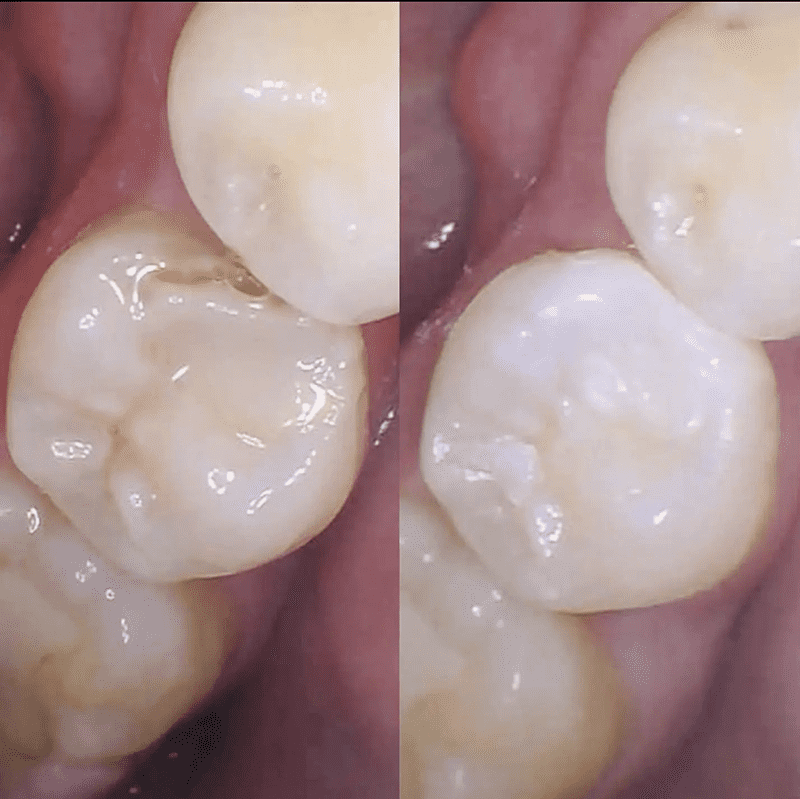

We offer state-of-the-art composite dental fillings in Leesburg, Virginia, as a core part of our comprehensive dental services. When cavities or tooth damage strike, composite fillings are a top-choice restorative solution, blending seamlessly with your natural teeth for both aesthetic and functional advantages.

- Aesthetic Appeal: These fillings are color-matched to your natural teeth, making them virtually indistinguishable. Say goodbye to unsightly metal fillings.

- Conservation of Tooth Structure: Composite fillings bond directly to the tooth, requiring minimal removal of healthy tooth structure. This ensures your tooth remains strong and durable.

- A final shaping and polishing to create a seamless appearance.

- Natural appearance

- Minimal tooth removal

- Enhanced tooth strength